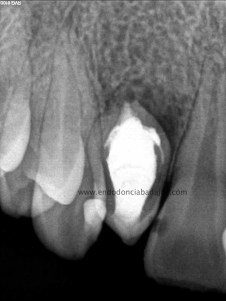

Como defensor del H de Ca ,en ciertas ocasiones, en este caso colocamos el mismo. En la siguiente cita, después de tallar el conducto, colocamos un sellado apical con cemento M.T.A. de varios milímetros y obturando con gutapercha inyectada con la pistola Obtura II.

Esperamos que tenga una evolución positiva y sino complementaremos el tratamiento con una microcirugía endodóntica.